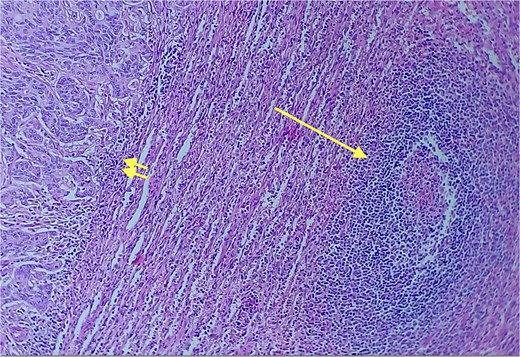

Given the histopathological findings, a laparoscopic splenectomy was performed in a second operative session. The procedure was carried out in the left lateral decubitus position using three trocars. Intraoperatively, a 3 × 3 cm lesion was identified within the splenic parenchyma. The specimen (Fig. 6) was extracted through the previously used Pfannenstiel incision. Histopathological analysis confirmed infiltration by an enteric-type adenocarcinoma (Figs 7–9).

Detail of an area of enteric-type adenocarcinoma composed of neoplastic proliferation of columnar epithelial cells with nuclear atypia, eosinophilic cytoplasm, and a complex tubular and cribriform arrangement with endoluminal necrosis; H&E ×400.